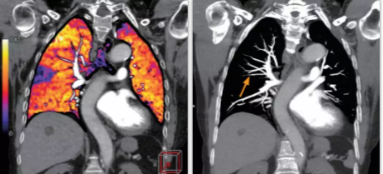

相比傳統(tǒng)成像方式,肺部柔性減影技術(shù)通過人工智能,對平掃數(shù)據(jù)和CT肺動脈血管掃描數(shù)據(jù)進(jìn)行智能比對,解碼并識別各個器官(肺、氣管、肺動脈、肺靜脈、主動脈等)的空間位置,并在三維空間中進(jìn)行體素級的柔性配準(zhǔn),從而極大提升了不同序列數(shù)據(jù)的空間位置的一致性。通過肺部柔性減影技術(shù)可得到肺強(qiáng)化碘圖,可以顯示出傳統(tǒng)CTPA圖像看不到的小栓塞病變,提高了栓塞檢出率,其結(jié)果甚至可與SPECT吻合。

肺智能柔性減影成像功能發(fā)現(xiàn)亞段肺栓塞